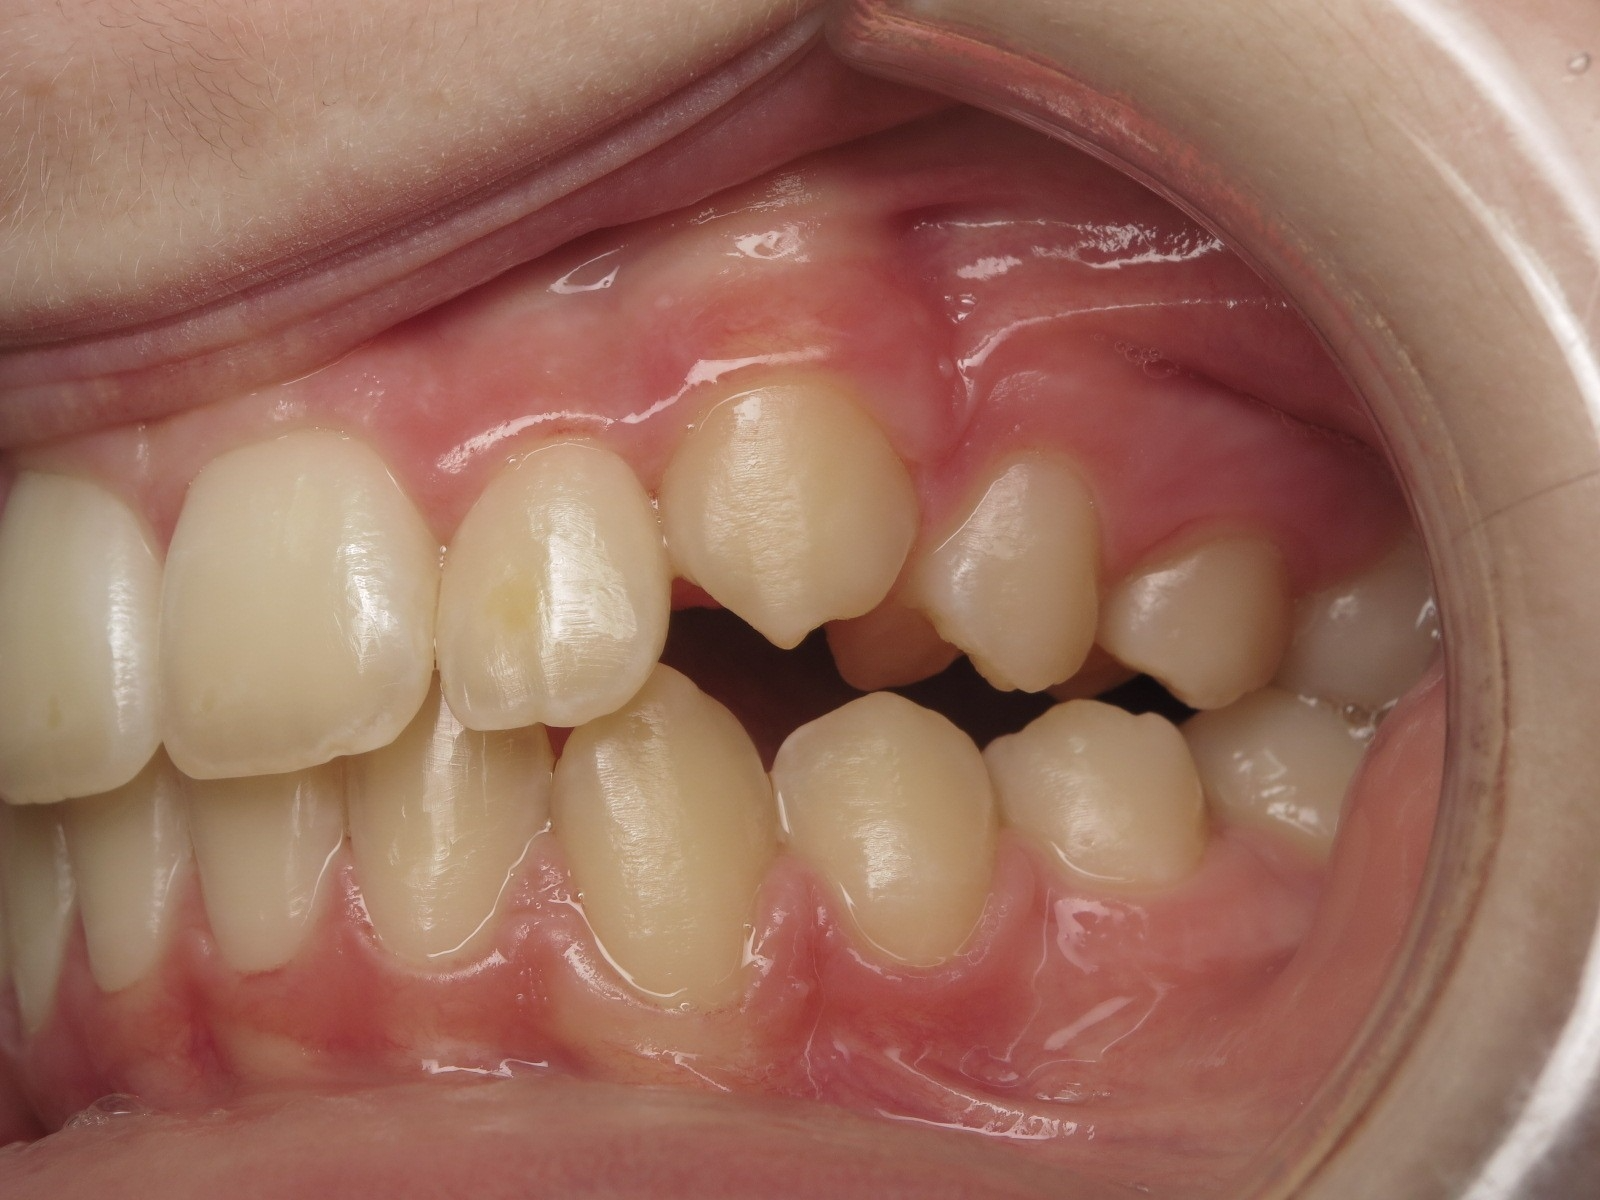

sectionnel multibagues

bilan début fin de traitement